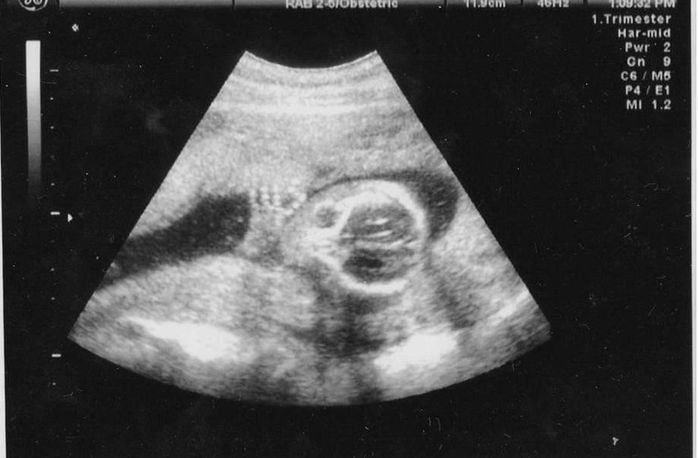

妊娠13週目のエコー写真

頭の大きさと体長から体重を割り出しています。